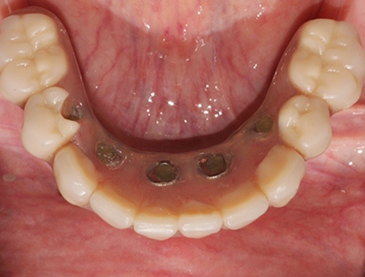

Fully edentulous clinical cases